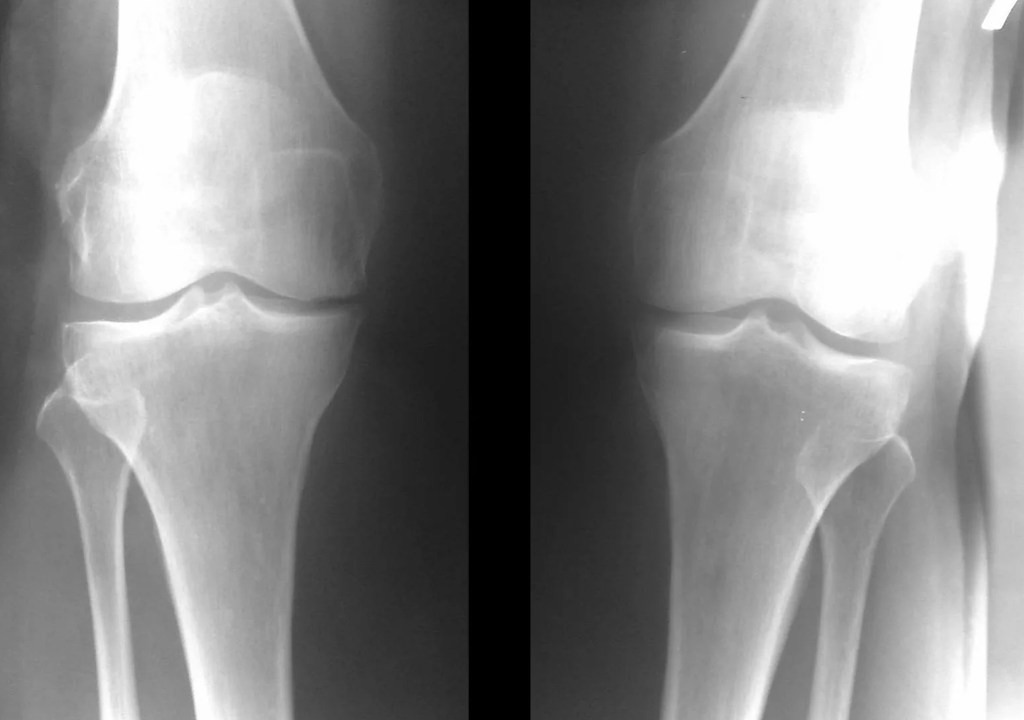

Instrumental diagnosis of arthrosis of the knee joint

In the vast majority of cases, an examination and x-ray of the knee joint in two projections (direct and lateral) are sufficient.Clinical data and images help determine the stage of the disease.

In the early stages of the disease, with minor changes in bone tissue, X-ray examination is not so valuable.At this stage, gonarthrosis can be diagnosed through arthroscopy.The accuracy of the method is very high; only its invasive nature and price can stop it.

Ultrasound does not allow clear visualization of changes in articular cartilage and intra-articular structures.Using MRI, you can detect changes in the bone, cartilage and soft tissue structures of the joint, as well as subchondral bone, with 85% accuracy.Scintigraphy can be used to assess the metabolic activity of periarticular bone tissue.